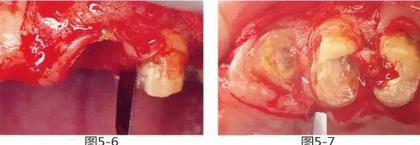

圖5-6,7

使用手術(shù)刀、7號牙齦刀、11號牙齦刀、咬骨鉗,盡可能將牙根周圍的軟組織進(jìn)行整體切除。